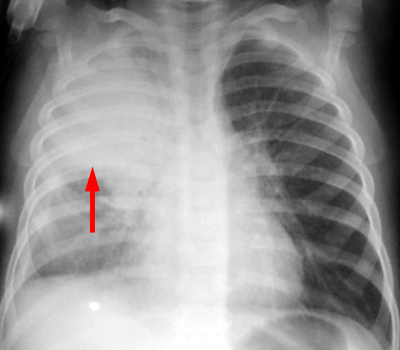

Initial CXR shows a dense right upper lobe consolidation.